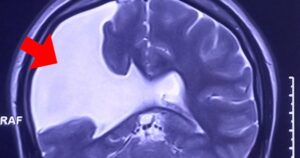

Người phụ nữ gần 30 năm sống chung với nứt não

Tối 10-11, Bệnh viện Đa khoa Tâm Anh TP HCM cho hay vừa mổ sọ[...]